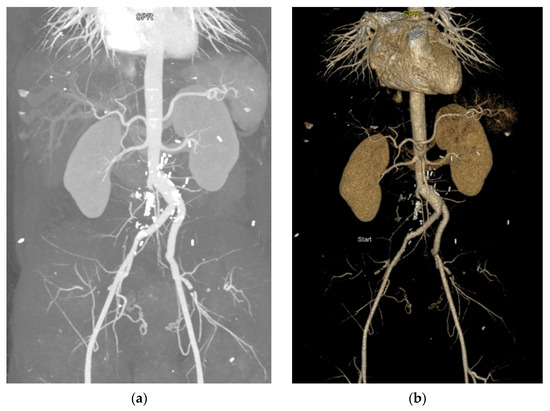

Chronic Complete Distal Aortic Occlusion and Pulmonary Embolism—Atypical Antiphospholipid Syndrome?

Caraiola, S.; Voicu, L.; Cașu, D.; Armășoiu, E.; Cobilinschi, C.O.; Mihai, E.; Ionescu, R.A. Chronic Complete Distal Aortic Occlusion and Pulmonary Embolism—Atypical Antiphospholipid Syndrome? Diagnostics 2023, 13, 1346. https://doi.org/10.3390/diagnostics13071346